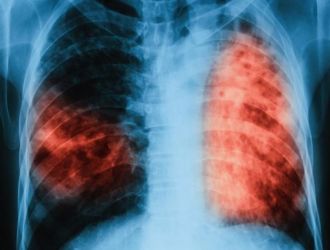

Четирима души от област Бургас са регистрирани с туберкулоза в последната седмица, сочи справка на БургасИНФО в бюлетина на РЗИ. Наскоро още двама души …